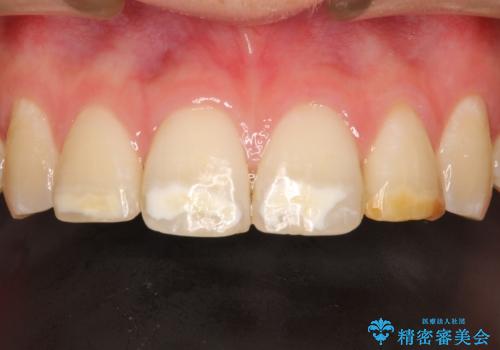

- 前歯をきれいにしたいとのご希望がありました。

生まれつき歯の色が白濁しているところや、黄色くなっているところがあり、セラミッククラウンに審美的改善を行うこととしました。